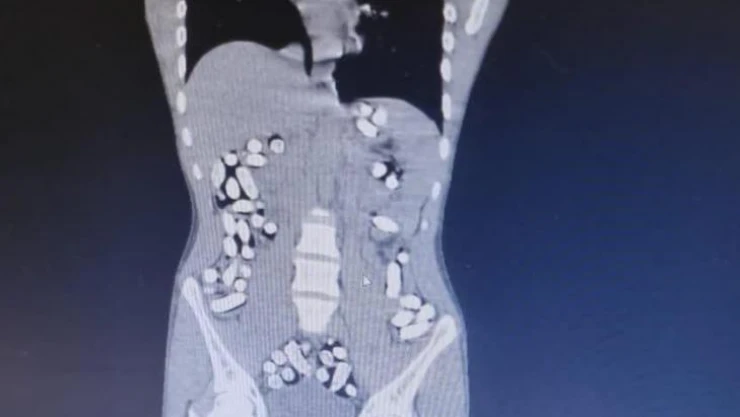

Erzurum Emniyet Müdürlüğü Narkotik Suçlarla Mücadele Şube Müdürlüğü ekipleri, batı illerine uyuşturucu madde nakli yapan şahıs ve araçlara yönelik Erzurum-Erzincan karayolu üzerinde yaptıkları denetimlerde İran’dan ülkeye giriş yapan bir yolcu otobüsünü durdurdu. Kontroller esnasında otobüsteki Mehdı B., Mılad F. ve Sıraus G. isimli şahısların hareketlerinden şüphelenen ekipler, şahısları iç beden muayenesi için hastaneye götürdü. Yapılan muayene ve röntgen çekimi sonrasında şahısların uyuşturucu maddeleri kapsül haline getirerek yuttukları tespit edildi. Doğal yollarla şahısların midelerinden çıkarılan 210 kapsül halinde 3 kilo 192,18 gram afyon sakızı ve 62 kapsül 709,83 gram eroin ele geçirildi.

Bir başka olayda, yine Erzurum-Erzincan karayolu üzerinde İran’dan ülkeye giriş yapan bir araç durduruldu. Araçta bulunan Masoud T. ve Soleman O. isimli şahısların şüpheli hareketler sergilemesi ve üzerlerinde tokluk hissi veren ve mide-bağırsak temizleyici ilaçlar bulunması sebebiyle yutmak suretiyle uyuşturucu madde nakli yaptıklarından şüphelenilerek, muayene için hastaneye götürüldü. Şahısların uyuşturucu maddeleri kapsül haline getirerek yuttukları tespit edildi. 411 kapsül halindeki 2 kilo 953 gram afyon sakızı ele geçirildi.